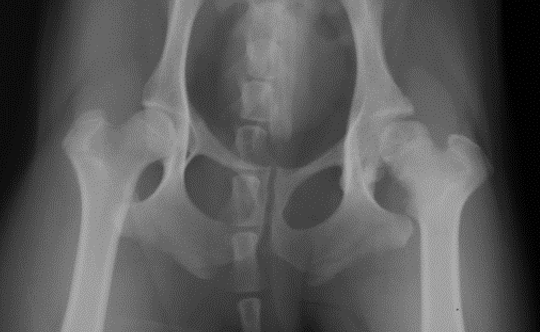

What is shown in this radiograph?

A

-normal right hip

-aseptic necrosis of femoral head in left hip

deformity and flattening of right femoral head due to aseptic necrosis of femoral head